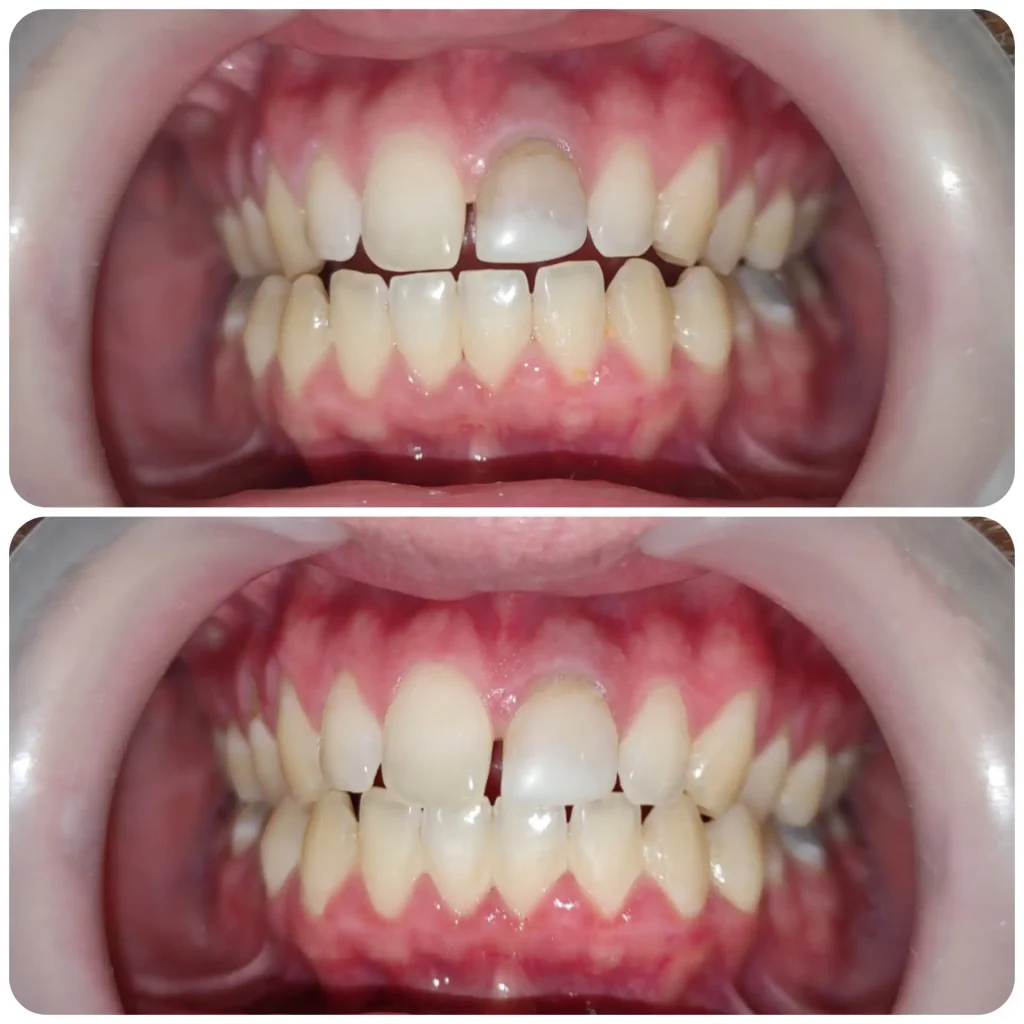

Esztétikai és fogmegtartó kezelések mellett nagy érdeklődéssel fordulok a fogszabályozás szakirány felé. Jelenleg fogszabályozási rezidensként sajátíthatom és mélyíthetem el tudásomat a harmonikus és funkcionálisan megfelelő harapás és esztétikai megjelenés kialakításában.

Szeretem felhívni a pácienseim figyelmét arra. hogy mekkora fontossággal bír egy megfelelően elvégzett fogszabályozási kezelés.